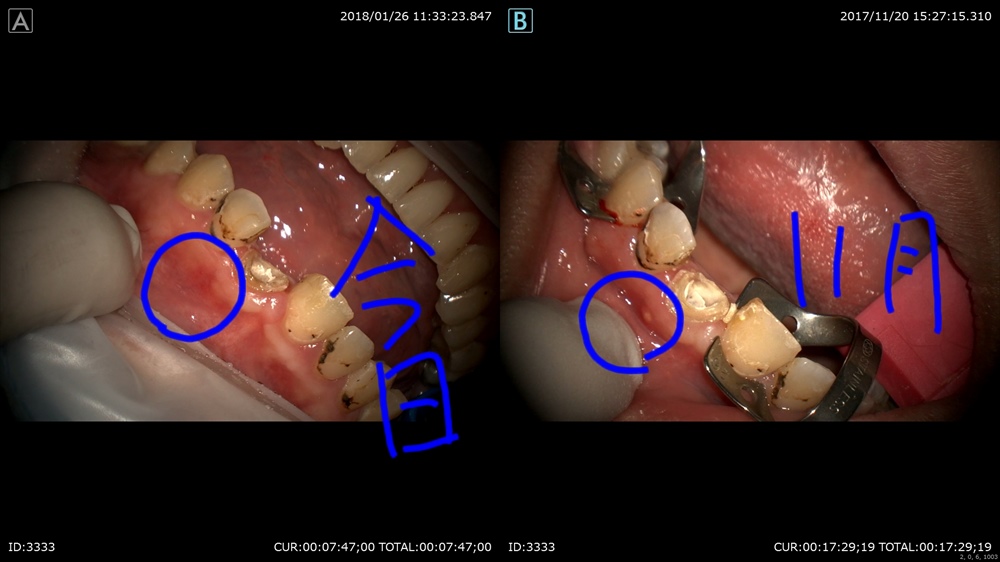

最後は精密根管治療 11月。はこの方重症のむし歯で歯茎がはれてます。

本日 きえたー。嬉しい!

比較